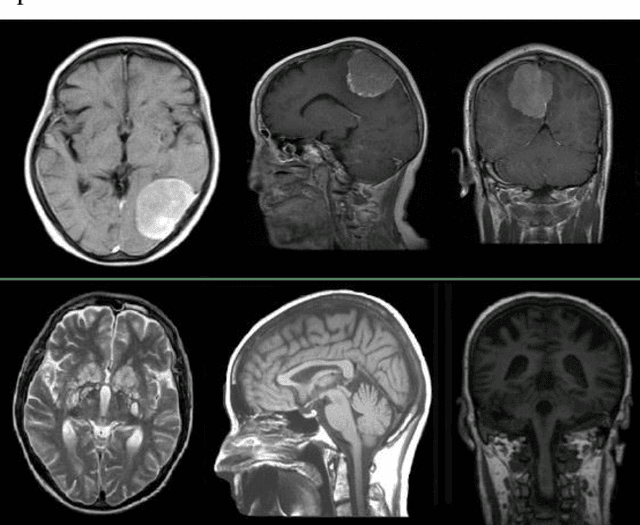

Accurate detection of brain tumors could save lots of lives and increasing the accuracy of this binary classification even as much as a few percent has high importance. Neural Gas Networks (NGN) is a fast, unsupervised algorithm that could be used in data clustering, image pattern recognition, and image segmentation. In this research, we used the metaheuristic Firefly Algorithm (FA) for image contrast enhancement as pre-processing and NGN weights for feature extraction and segmentation of Magnetic Resonance Imaging (MRI) data on two brain tumor datasets from the Kaggle platform. Also, tumor classification is conducted by Support Vector Machine (SVM) classification algorithms and compared with a deep learning technique plus other features in train and test phases. Additionally, NGN tumor segmentation is evaluated by famous performance metrics such as Accuracy, F-measure, Jaccard, and more versus ground truth data and compared with traditional segmentation techniques. The proposed method is fast and precise in both tasks of tumor classification and segmentation compared with other methods. A classification accuracy of 95.14 % and segmentation accuracy of 0.977 is achieved by the proposed method.